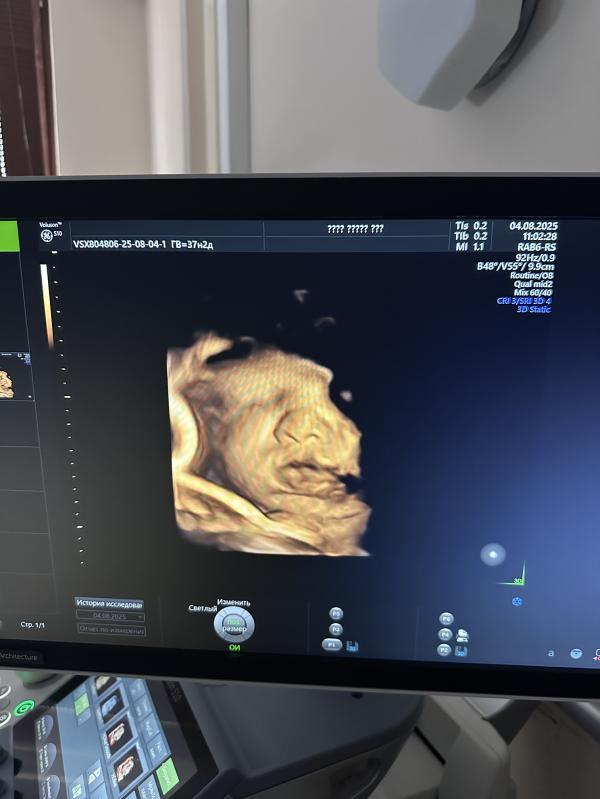

Вот такая губастик 🤗🙈😻

Ага, сегодня в полном восторге 🫣😻 смотрю на эти фото и умиляюсь 😍 Носик мой 🙈 губки папины 😍👌